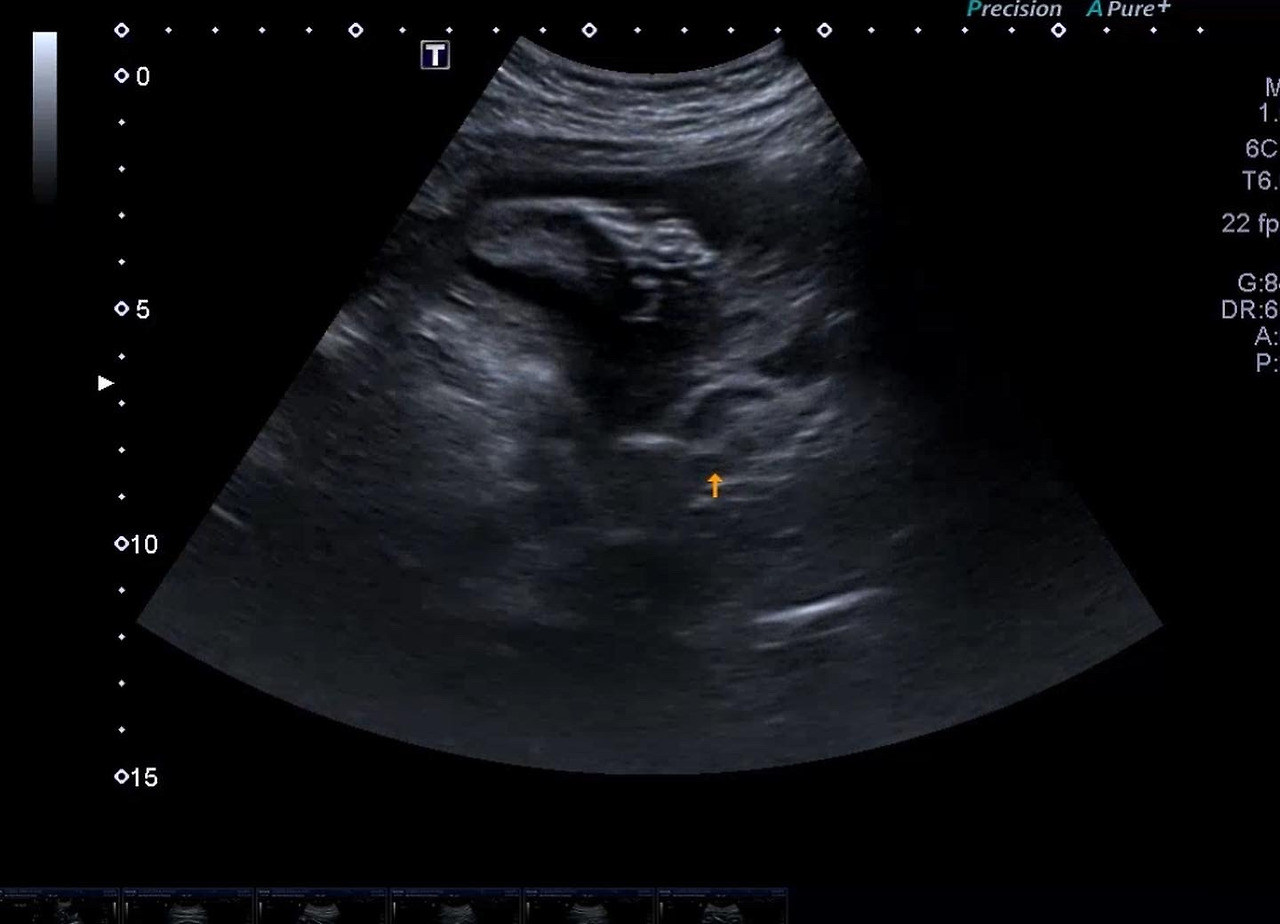

다올이 발

29주 발.jpg

이건 아마 발? 이었던거 같은데..

다올이는 늘 발이 얼굴 쪽에 있다. 얼마나 유연한 거니 아가..!